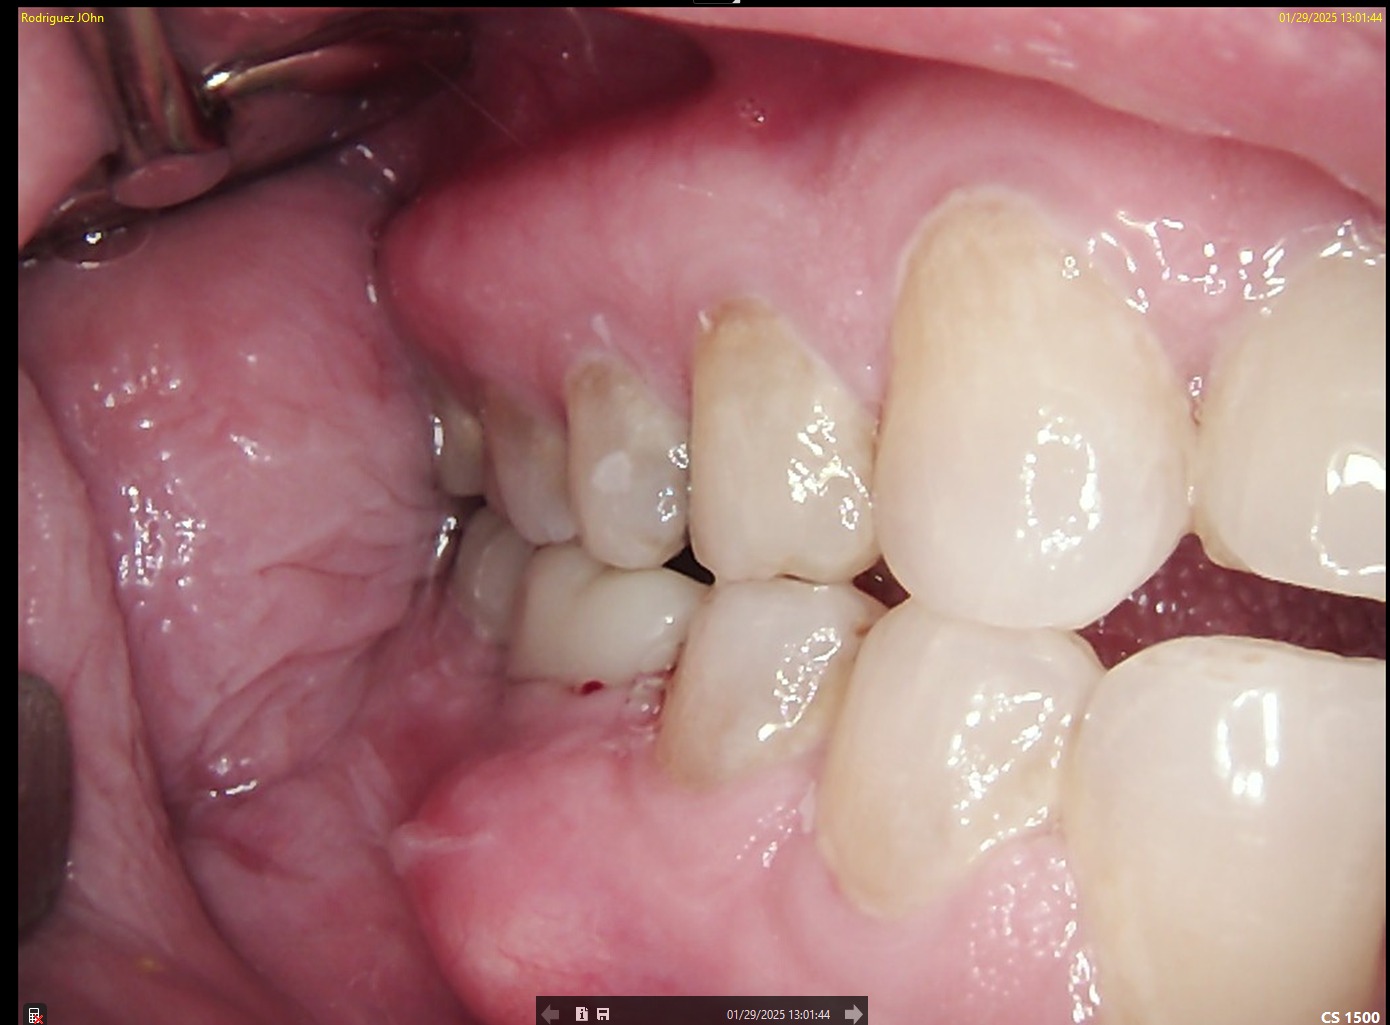

FOLLOW-UP - 2025

At the two-year follow-up:

• Continued soft tissue stability was observed

• No signs of peri-implant bone loss

• Prosthetic components remained intact and functional

Radiographic analysis confirmed long-term osseointegration and biological stability.